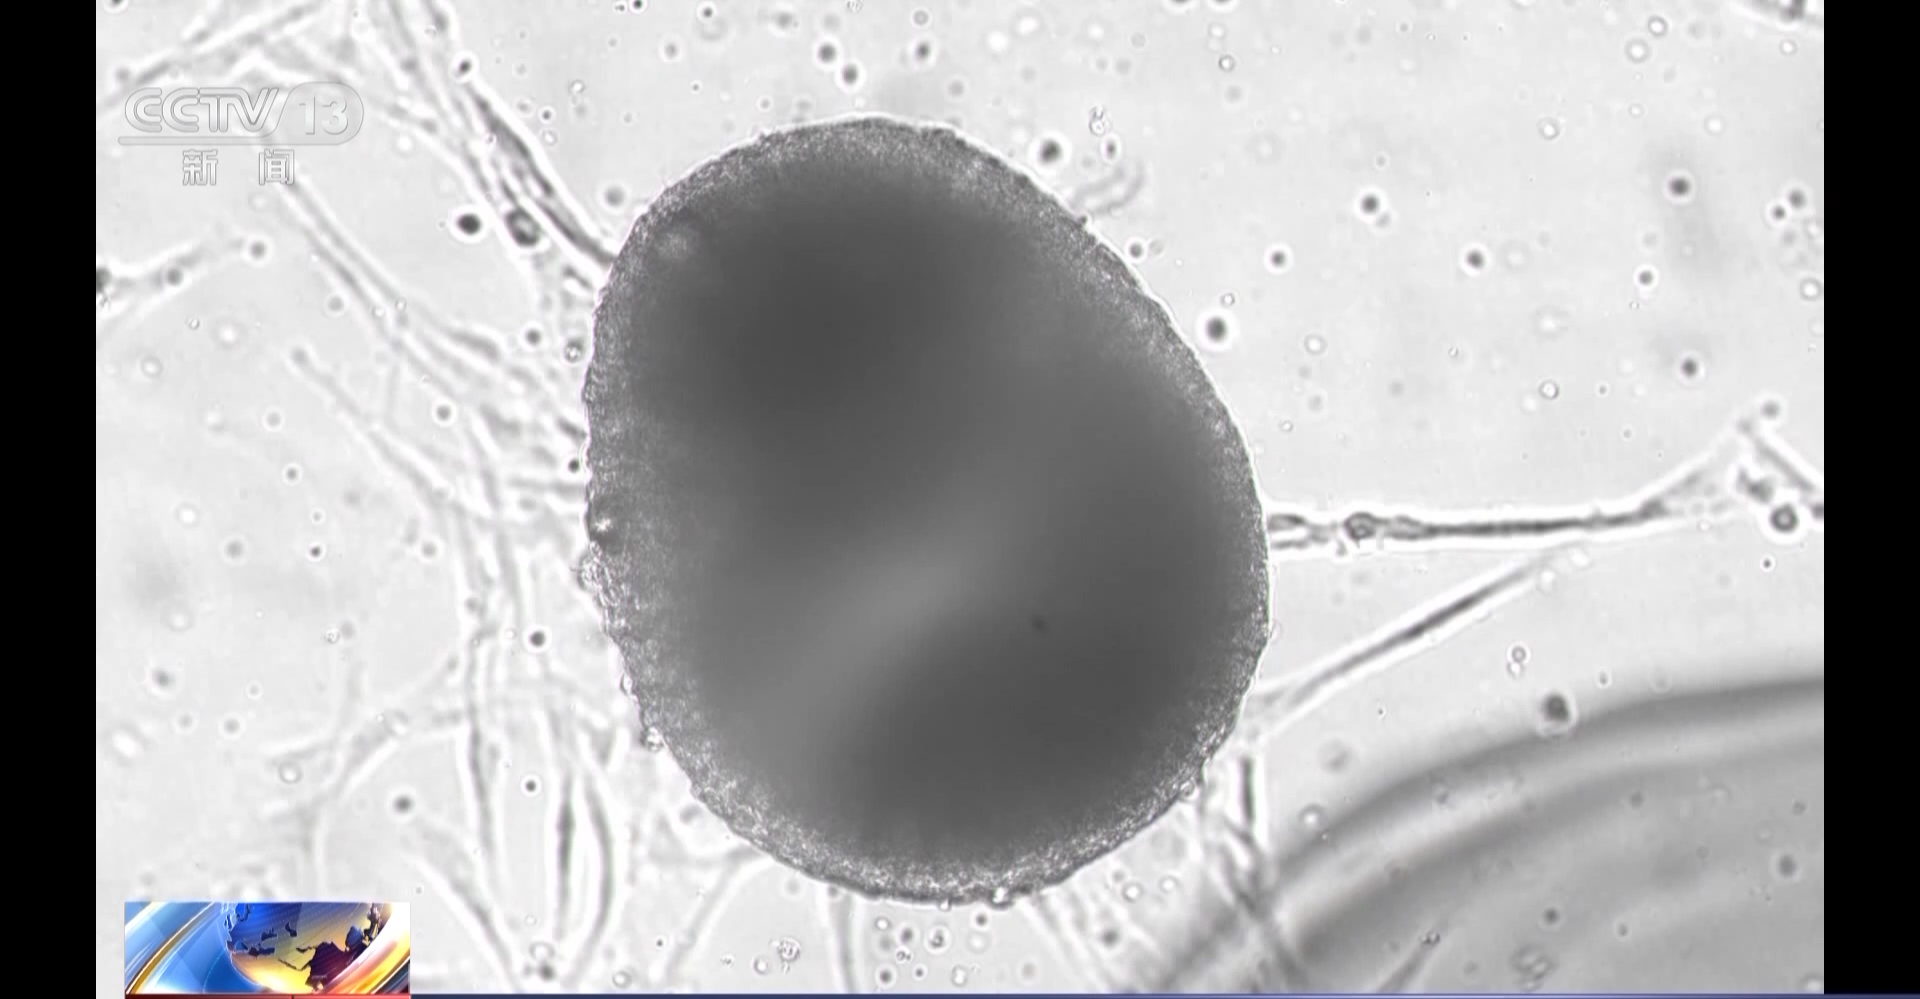

目前,我国已在轨实施了多个航天医学细胞学实验项目,不仅为航天员的身体健康防护提供了重要的研究平台,也可为大众健康作出贡献。

在轨细胞学实验为从器官、组织、细胞和分子水平研究空间失重等因素对机体的影响机制、开展针对性的防护等提供了理论和实验依据。在神舟十三号、十四号、十五号、十六号和天舟五号5次飞行任务中,将8种细胞和人工血管芯片送上太空,在轨共开展了10项细胞学实验研究,从在轨实验技术、实验模型和科学研究等多方面取得了系列创新性成果。

目前我国将人多能干细胞来源心肌细胞、皮肤干细胞、成骨细胞、人骨骼肌卫星细胞等细胞和人工血管芯片送上太空,在轨开展了微重力诱导心血管紊乱的细胞学机制及其防护药物筛选、空间微重力环境下皮肤干细胞的生物学效应与分子机制等细胞学实验研究。